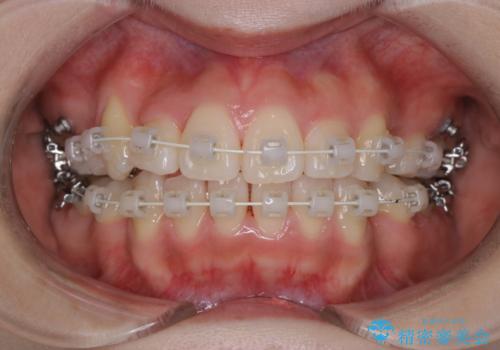

【ワイヤー矯正】オープンバイトを治したい

- 4番の歯を4本抜歯をし、上顎にマイクロインプラントを2本埋入し、遠心移動を行いました。

主訴のオープンバイトは改善し、抜歯をしたことで前歯が下がり綺麗になりました。抜歯矯正でしたが1年2か月という短い期間で終了しました。